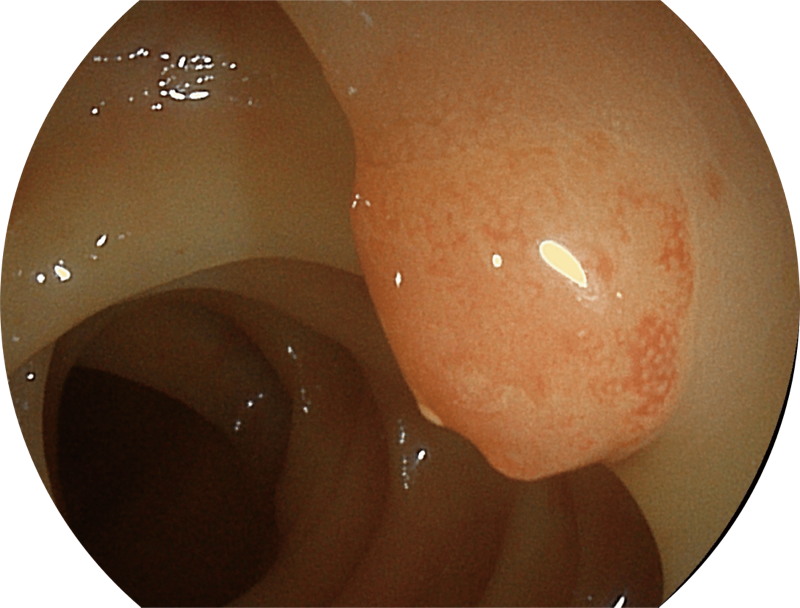

百万级像素高清传感器,1080P全高清视频信号输出,图像清晰。

白光图像

白光图像